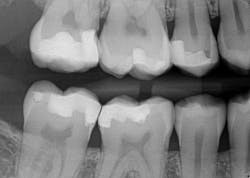

Caries lesions were removed and air abrasion was employed to remove impurities on the unprepared tooth surfaces and create increased surface area for bonding. Preparation of the class II carious lesions revealed demineralization on the adjacent tooth structure (figure 3). When lesions such as these are discovered, dentists are often at a crossroads whether to intervene or monitor the area for progression. It is my experience that these early caries lesions can be predictably arrested with resin infiltration (figure 4), and that no intervention usually results in the progression of caries.